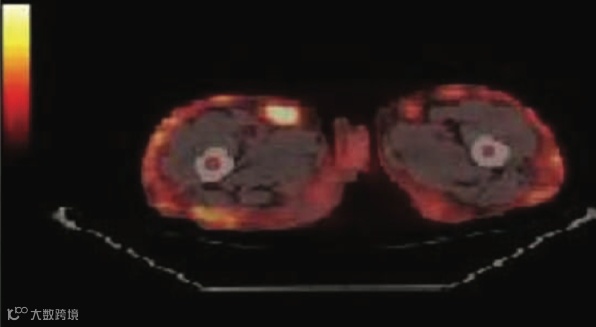

之所以叫“虎纹”,是因为病灶呈现出“条纹状、线状” (Linear/Stripe-like) 的特征。请仔细看四肢,高代谢灶是顺着肢体长轴分布的,就像老虎身上垂直的斑纹。

“虎纹”是肌肉的纹理。这种征象的核心病理基础是肌肉受累(Muscular involvement)。FDG 沿着肌束(Muscle fascicles) 进行弥漫性或多灶性的浸润。